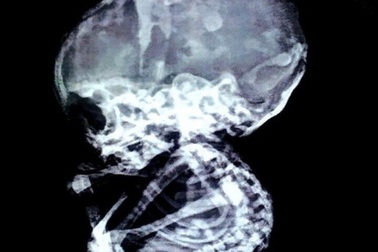

15 năm sau khi nạo thai, sốc vì bào thai vẫn còn nguyên trong bụng mẹ, hóa đáMột phụ nữ người Ấn Độ từng phải lựa chọn phá thai bởi gia đình không chấp nhận đứa trẻ thế nhưng 15 năm sau, các bác sĩ lại ngỡ ngàng phát hiện ra thai nhi vẫn còn nằm trong bụng mẹ.